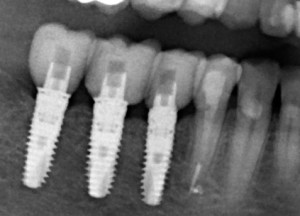

Когда мы говорим об ультракоротких (7 мм и менее) имплантах, то в первую очередь на ум приходит Bicon:

![]()